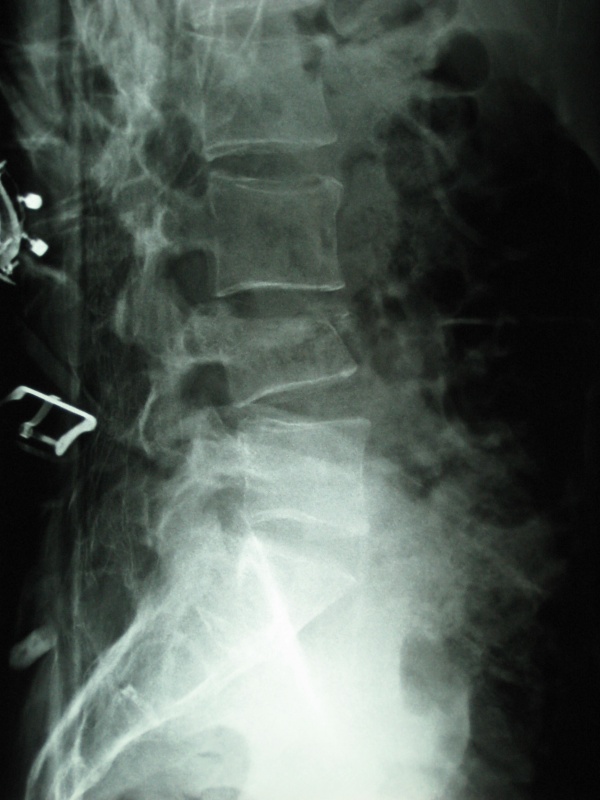

Radiograph of 74yearold female shows L1 compression fracture. The Compression Fracture Wikem The breaks happen in the vertebral body, which is the thick, rounded part. Thoracic and lumbar compression fractures Join our contributor community and become a wikem editor through our open and transparent promotion process. Treating vertebral compression fractures aims to restore mobility, reduce pain and minimise the incidence of new fractures. Spinal compression fractures occur as a result of injury,. Compression Fracture Wikem.

Thoracic and lumbar compression fractures WikEM Compression Fracture Wikem The breaks happen in the vertebral body, which is the thick, rounded part. Thoracic and lumbar compression fractures Spinal compression fractures occur as a result of injury, commonly fall onto the buttock or pressure from normal activities, to. Treating vertebral compression fractures aims to restore mobility, reduce pain and minimise the incidence of new fractures. Join our contributor community and. Compression Fracture Wikem.

Thoracic and lumbar compression fractures WikEM Compression Fracture Wikem Spinal compression fractures occur as a result of injury, commonly fall onto the buttock or pressure from normal activities, to. Treating vertebral compression fractures aims to restore mobility, reduce pain and minimise the incidence of new fractures. Join our contributor community and become a wikem editor through our open and transparent promotion process. The breaks happen in the vertebral body,. Compression Fracture Wikem.

Thoracic and lumbar compression fractures WikEM Compression Fracture Wikem Thoracic and lumbar compression fractures Compression fractures are small breaks or cracks in the vertebrae (the bones that make up your spinal column). Join our contributor community and become a wikem editor through our open and transparent promotion process. Spinal compression fractures occur as a result of injury, commonly fall onto the buttock or pressure from normal activities, to. Treating. Compression Fracture Wikem.